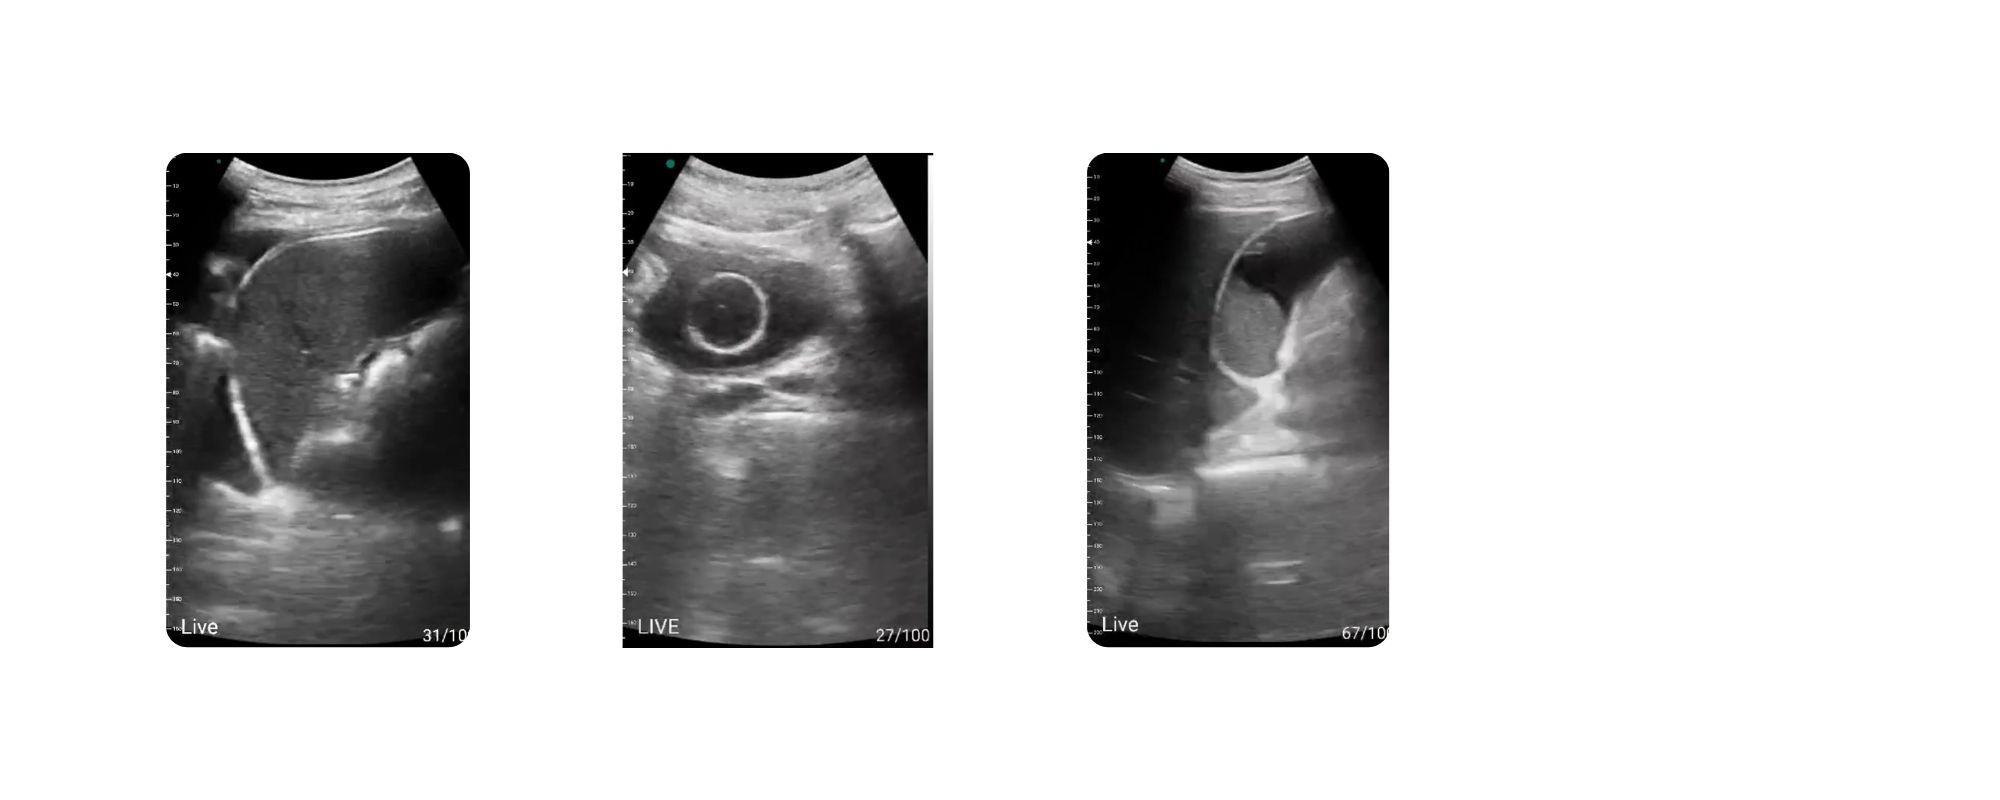

پروب CLP4 با داشتن ۱۲۸ پیزوالکتریک و قابلیت تصویربرداری در مدهای مختلف رنگی و پالس بعلاوه موشن و دیگر مدها از کیفیت تصویر بسیار خوبی برخوردار است و در زمینههای مختلف سونوگرافی قابل استفاده میباشد:

سونوگرافی شکمی شامل بررسی کبد، کلیهها، طحال، مثانه، صفرا و سایر ارگانهای داخلی

تصویربرداری از اندامهای سطحی مانند عروق، تاندونها، عضلات و مفاصل

سونوگرافی اطفال به دلیل اندازه کوچک پروب و کنترل آسانتر آن در دستان پزشک

3. زنان و زایمان (OB/GYN)

سونوگرافی هندهلد CLP4 برای مادران باردار و متخصصین زنان کاربردهای وسیعی دارد:

-

ارزیابی اولیه وضعیت جنین

بررسی ضربان قلب جنین (FHR)

بررسی سلامت جفت و میزان مایع آمنیوتیک

تشخیص سقط، بارداری خارج از رحم، یا خونریزیهای داخلی

بررسی کیست، فیبروم، ضایعات رحمی و تخمدانی

4. نفرولوژی و اورولوژی

تشخیص بیماریهای کلیه، مجاری ادراری و پروستات با CLP4 بسیار دقیق و سریع انجام میشود:

بررسی سایز و اکوی کلیه

تشخیص سنگ کلیه

تشخیص هیدرونفروز

بررسی مثانه، پروستات و باقیمانده ادرار (PVR)

ارزیابی انسدادها یا تودههای احتمالی